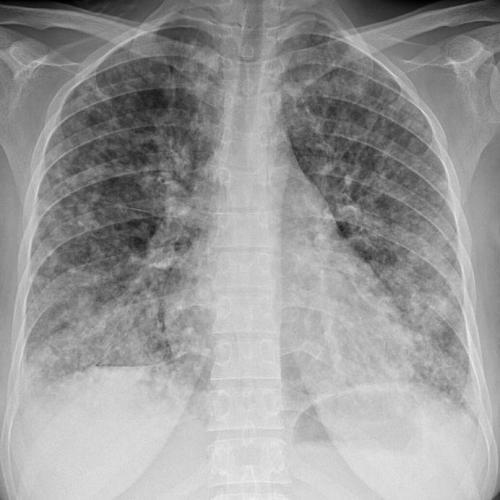

У трети пациентов наблюдаются незначительные признаки поражения органов дыхания. Особенностью туберкулеза легких является отсутствие симптомов или минимальное их проявление. В основном его выявляют при профилактических осмотрах. Основную картину туберкулеза дает рентгенография легких, но она имеет различие в зависимости от фазы и продолжительности процесса.

Сравнивая КТ легких при пневмонии с обычным рентгенологическим исследованием, преимущества томографии очевидны: более высокая чувствительность и точность. Она позволяет обнаружить наиболее мелкие детали патологического процесса, не давая усомниться в диагнозе. Однако исследование не так доступно и сопряжено с более существенной лучевой нагрузкой на пациента.

Почему возникают и чем опасны очаги в легких

Очаговые образования в легких — уплотнение ткани, вызываемое различными заболеваниями. Обычно они выявляются в результате рентгенологического исследования. Иногда осмотра специалиста и методов диагностики бывает недостаточно, чтобы сделать точное заключение. Для окончательного подтверждения нужно провести специальные методы обследования: анализы крови, мокрот, пункцию тканей. Происходит это при злокачественных опухолях, пневмонии и нарушении обмена жидкости в дыхательной системе.

Компьютерная томография способна с большей вероятностью установить размер, форму уплотнения легочной ткани. Это исследование тоже обладает процентом погрешности.

Очаговые образования в органах дыхания представлены в качестве дегенеративных изменений в тканях легких или скапливании жидкости в виде мокроты или крови. Многие специалисты считают одной из важных задач их установление.

До 70% одиночных очагов в легких относятся к злокачественным новообразованиям. С помощью КТ (компьютерной томографии), и базируясь на специфических симптомах, специалист может предположить о возникновении таких опасных патологий, как туберкулез или рак легких.

Провести аппаратным методом четкую диагностику заболевания не позволяет несовершенство оборудования. При прохождении рентгенографии легких трудно обнаружить очаговые изменения, размер которых не достигает 1 см. Интерпозиция анатомических структур делает невидимыми и более крупные образования.